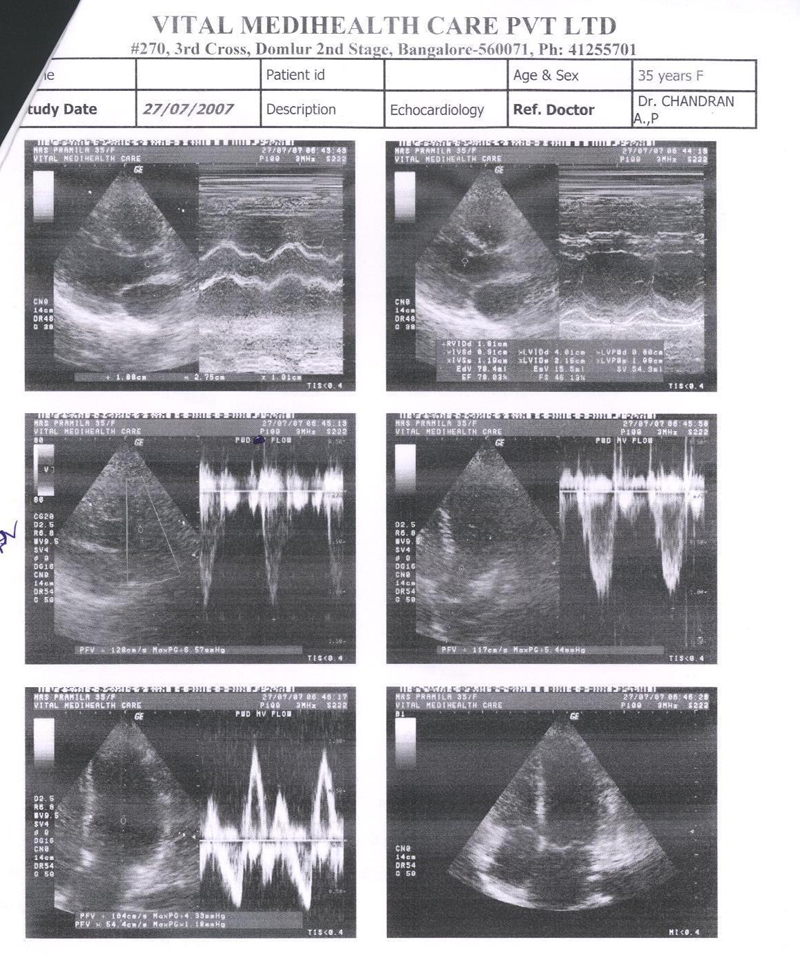

Echocardiography was done and shows that the valves are much better, the abnormal murmur heard using stethoscope have almost disappeared. Echocardiography report is shown in FIG3. Placebo continued

FIG 3:- Echocardiography report of 27th Nov. 2007